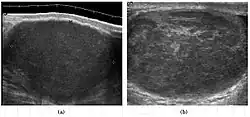

Epididymo-orchitis in a 77-year-old man. (a) Transverse sonography shows enlargement of the epididymis with hypoechogenicity noted over the testis and epididymis associated with scrotal wall thickening. (b) Color Doppler sonography showed hyperemic change of the testis and epididymis, presenting as an “inferno” vascular flow pattern.

Epididymitis and epididymo-orchitis are common causes of acute scrotal pain in adolescent boys and adults. At physical examination, they usually are palpable as tender and enlarged structures. Clinically, this disease can be differentiated from torsion of the spermatic cord by elevation of the testes above the pubic symphysis. If scrotal pain decreases, it is more likely to be due to epidiymitis rather than torsion (Prehn's sign). Most cases of epididymitis are secondary to sexually transmitted disease or retrograde bacteria infection from the urinary bladder.[6] The infection usually begins in the epididymal tail and spreads to the epididymal body and head. Approximately 20% to 40% of cases are associated with orchitis due to direct spread of infection into the testis.

At ultrasound, the findings of acute epididymitis include an enlarged hypoechoic or hyperechoic (presumably secondary to hemorrhage) epididymis [Fig. 20a]. Other signs of inflammation such as increased vascularity, reactive hydrocele, pyocele and scrotal wall thickening may also be present. Testicular involvement is confirmed by the presence of testicular enlargement and an inhomogeneous echotexture. Hypervascularity on color Doppler images [Fig. 20b] is a well-established diagnostic criterion and may be the only imaging finding of epididymo-orchitis in some men.